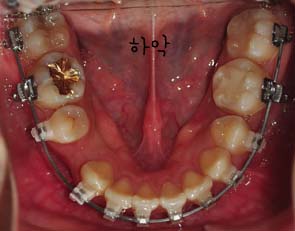

사진과 같이 보시면 입천장에 스크류가 심어졌을때의 모습이 보이시나요? 사진과 같이 두개의 스큐르를 심은후 고무로된 연결고리로 연결하여 킬본교정장치에 걸어서 당기고 당기고~ 를 해주는겁니다 *,*

저는 스크류 2개를 입천장에 심어서 이것을 킬본교정장치와 연결아서 당김으로써 앞니가 들어가는것에 효과를 주도록 하였는데요